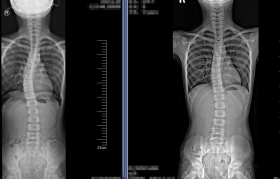

2. 度数迷思的破除 20度以下:通过瑜伽、游泳等对称性运动可完全矫正...

201